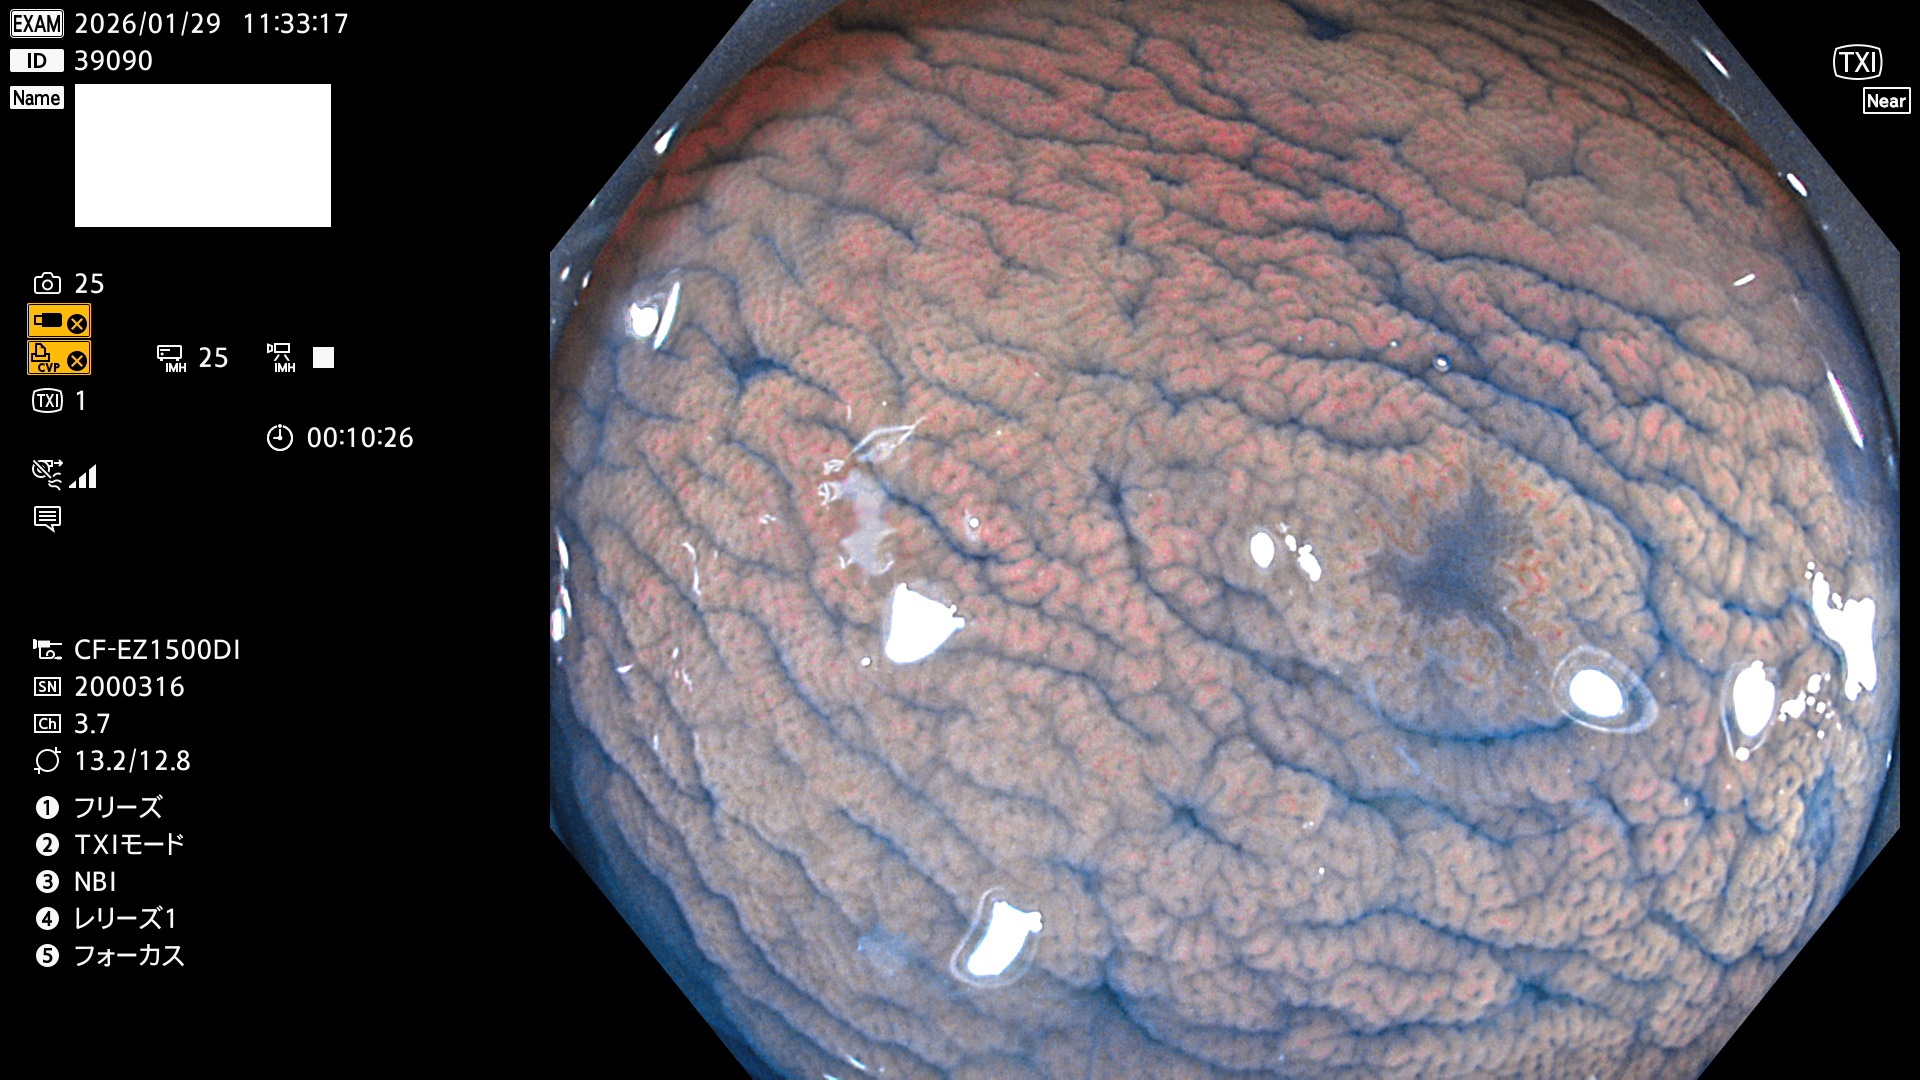

完全に平坦な物をUb、陥凹している物をUcと呼びます。Ubは認識が困難で、Ucはびらん(炎症)と紛らわしいために見落とされやすく、「内視鏡後・大腸癌」の原因になります。

専門的)Uc=De Novo癌? 内視鏡の解像度が低かった時代、このような説もありました。しかし今日の高精度内視鏡では良性の微小なUc型腺腫(APC遺伝子異常の腺腫)が日常的に見つかります。Ucこそが多段階発癌(Adenoma-Carcinoma Sequence)のMain Routeです。

毎週の検査(木・金・土・日)に発見されたUbとUc型・腺腫を、その週の日曜の夜にUPし1週間、提示します。

2026年1月29日〜2月1日の4日間(40件)10個 (Uc_ADR=10個/40人=25%)